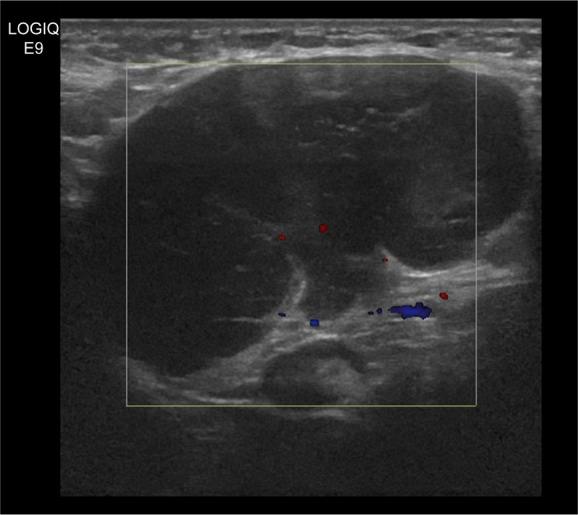

隐匿性乳腺癌的定义为存在腋窝转移但未发现原发性乳腺肿瘤。在此,我们报告一例罕见的男性隐匿性乳腺癌合并皮肌炎病例。我们实施了改良根治性乳房切除术,包括全乳切除术和腋窝淋巴结清扫术。免疫组织化学和荧光原位杂交分析显示为可能起源于乳腺的腺癌,即隐匿性三阴性乳腺癌。有趣的是,患者先前出现的眶周皮肌炎在手术切除后迅速缓解。

Sonographic findings of axillary masses: what can be imaged in this space?腋窝肿块的超声表现:这个部位能显示哪些影像?

J Ultrasound Med. 2013 Jul;32(7):1261-70. doi: 10.7863/ultra.32.7.1261.